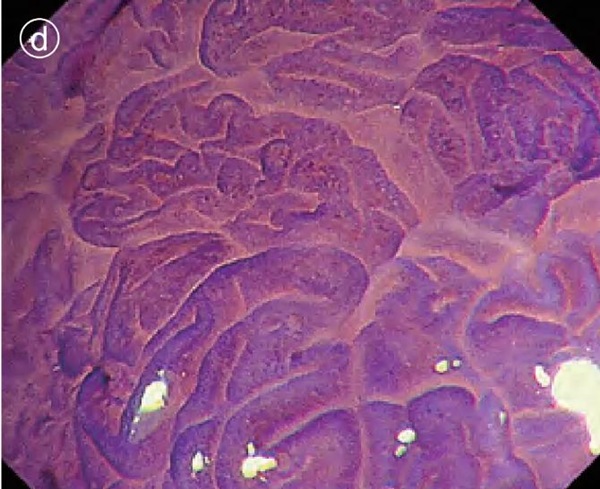

d. Enlarged image of crystal violet staining

The pit pattern of the glandular duct opening at the edge of the lesion was type IV.